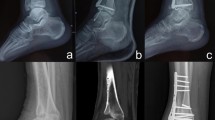

Figure 1 shows the deviation color maps of two exemplary subjects within the control group. The left–right surface differences of the distal tibia and fibula were very small in the control group. Figure 2 shows the weight-bearing plain radiographs and bone surface models reconstructed based on CT data of the OA-side in six representative cases. The deviation color map of almost all cases of all stages showed surface depression on the medial articular surface of the medial malleolus and surface elevation along the anterolateral margin of the distal tibia (Fig. 3). In stage 3b, some surface depression on the middle of the anterior area of the plafond was observed. However, the change in the surface of the medial and posterior areas of the plafond was found to be small (< 0.6 mm) compared with that of the articular surface of the medial malleolus (See below for quantitative comparisons). In addition, surface elevation on the anterior borders of the lateral malleolus and the distal tibiofibular articular surface was found.

Deviation color maps of left–right comparisons of the tibia and fibula in the OA group. Six representative cases (the same cases as in Fig. 1) are presented. The red and blue colors are deviations of the OA surface outside and inside of the opposite surface. 1. Anterior view. 2. Posterior view. 3. Inferior view. y/o = years old. See text for more details.